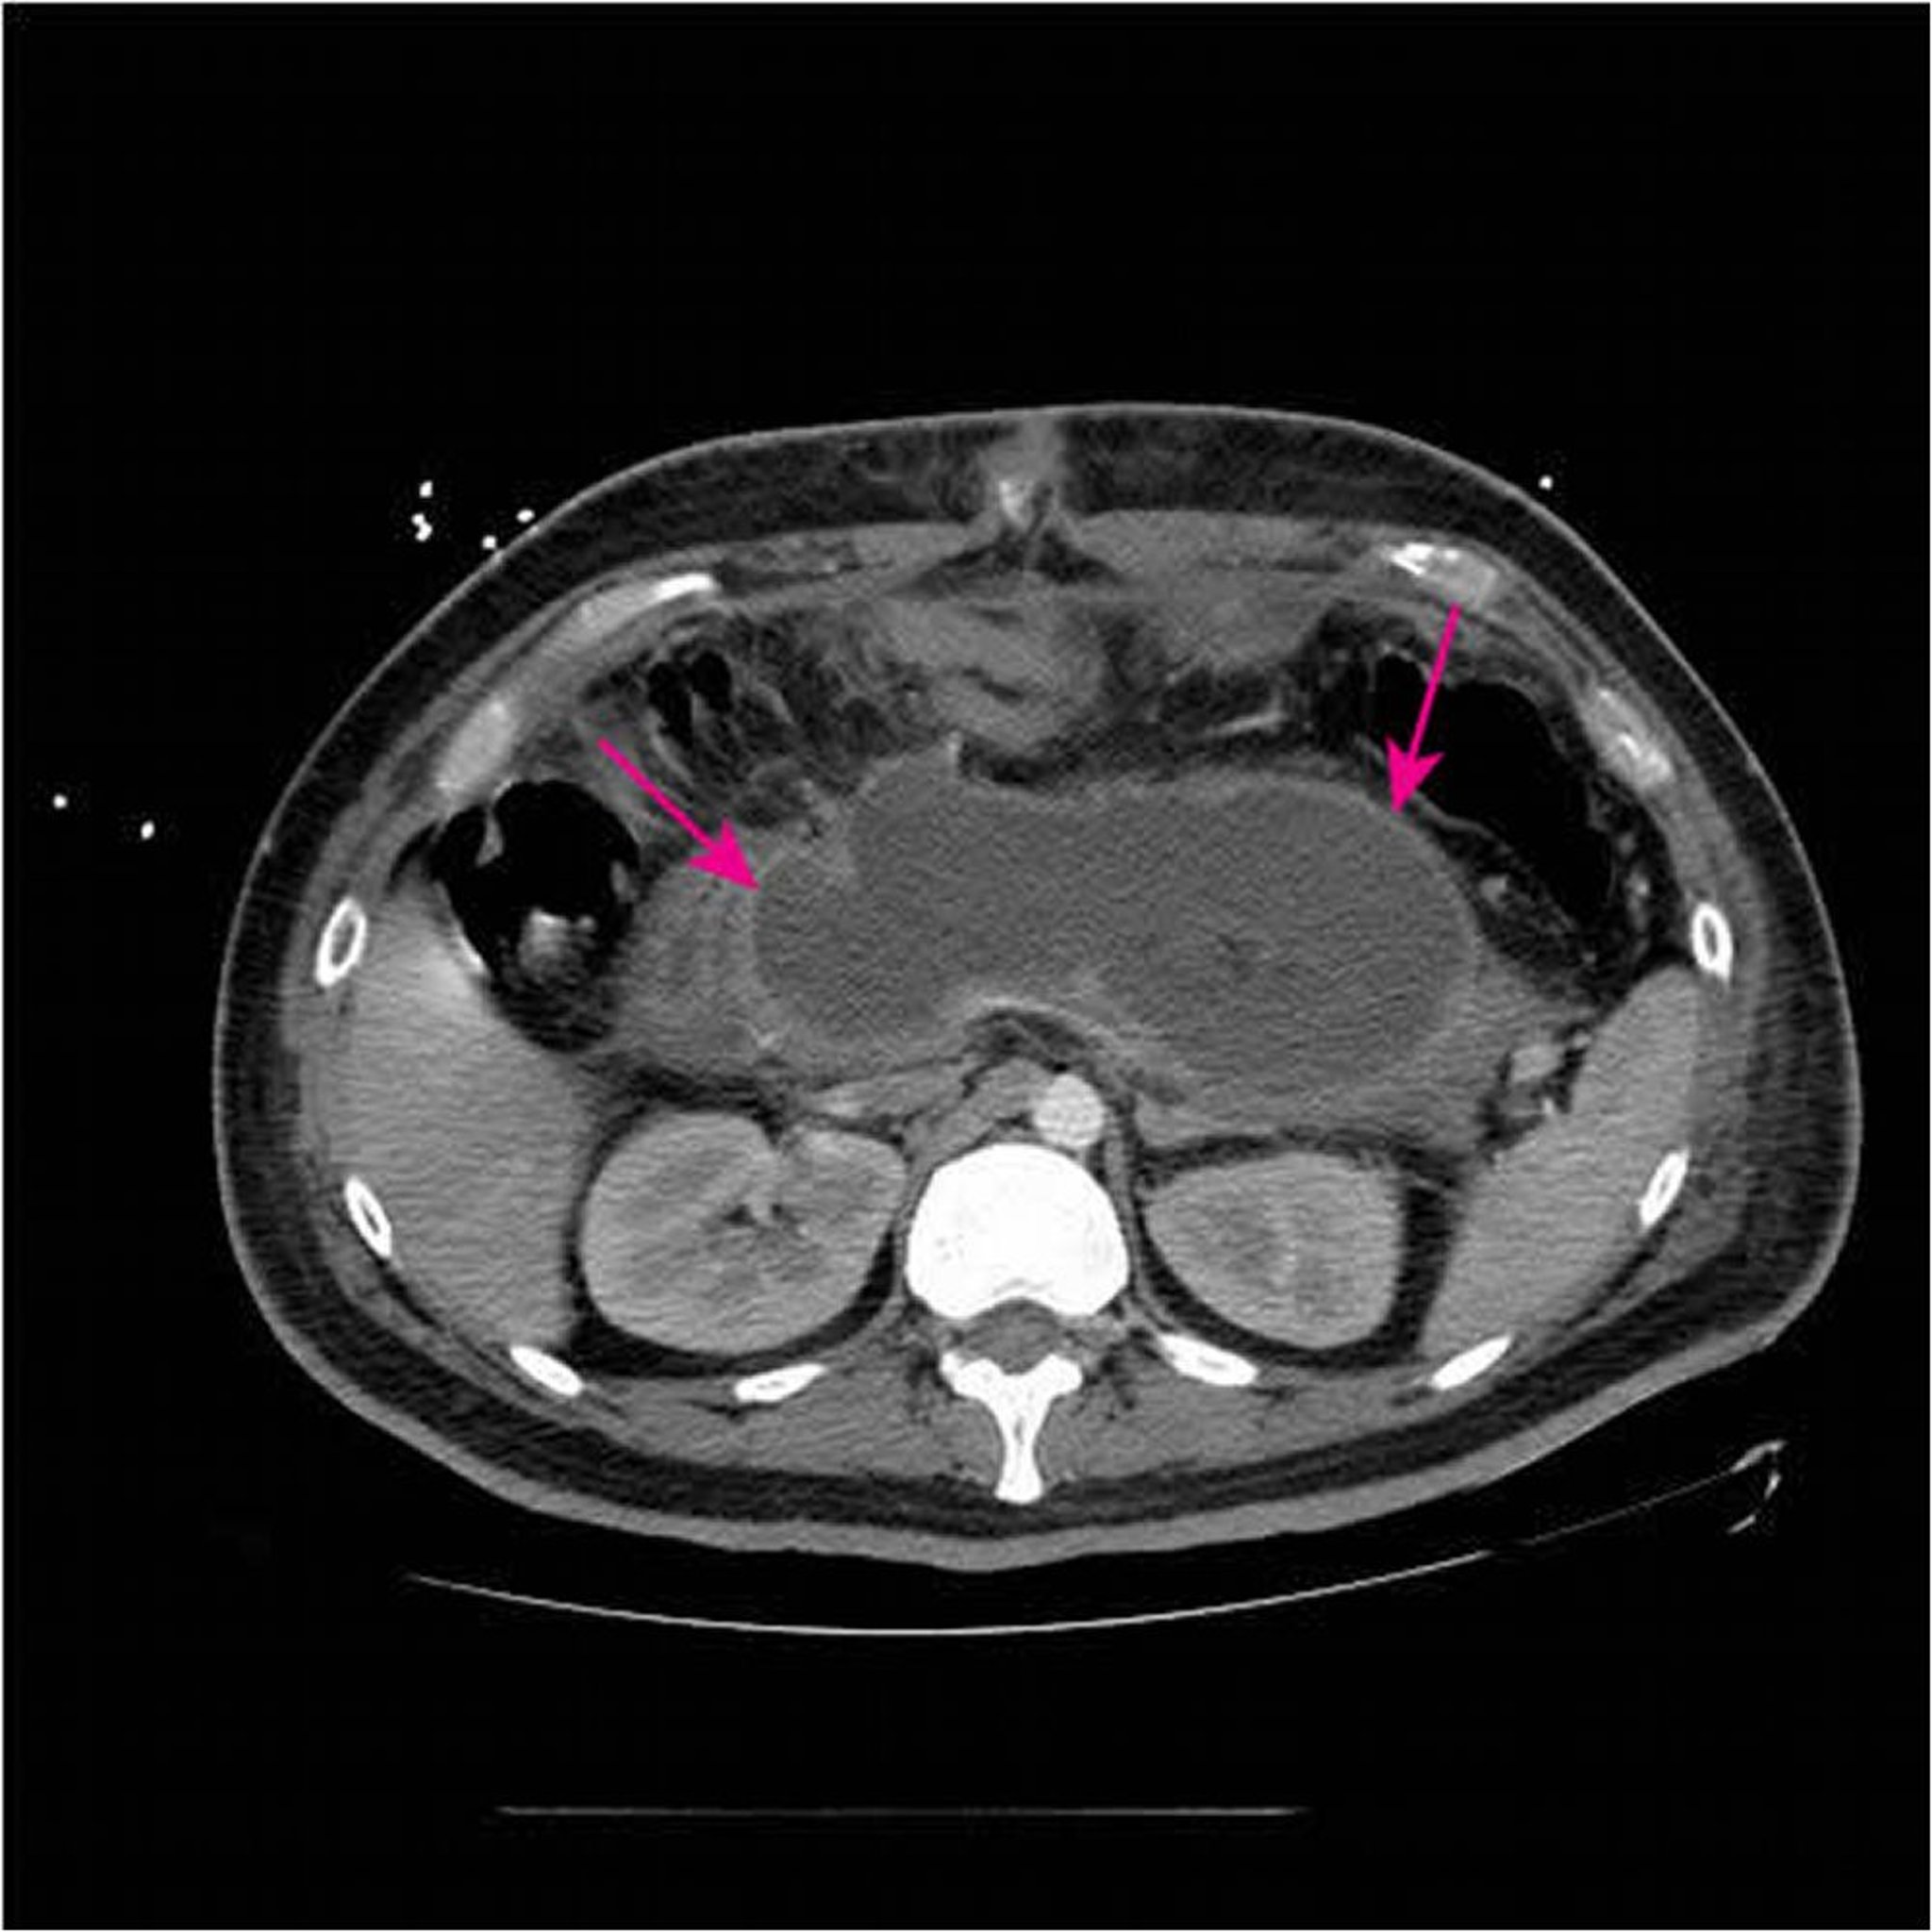

Ổ tụ dịch hoại tử cấp

Chụp CT có thuốc cản quang đường tĩnh mạch và đường uống cho thấy một ổ tụ dịch hoại tử cấp tính lớn (mũi tên) thay thế hầu hết các mô tụy < 4 tuần kể từ khi có biểu hiện ban đầu của viêm tụy hoại tử.

Hình ảnh do bác sĩ Sonam Rosberger cung cấp